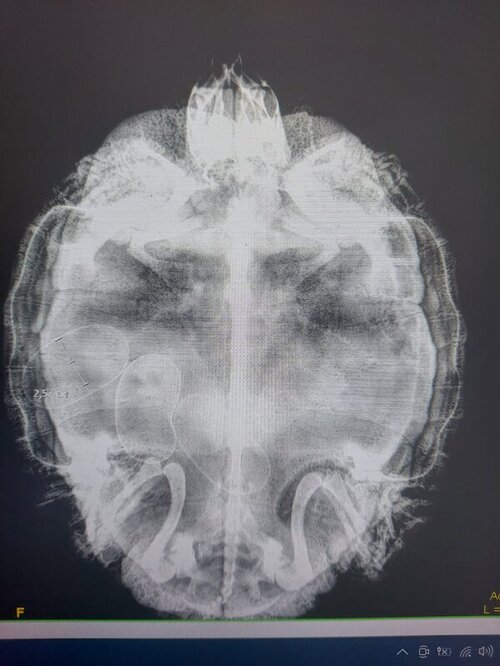

ArtyEgo Ваше имя: Андрей Локация: Россия, Владивосток Опубликовано: 21 марта 2022 Автор Опубликовано: 21 марта 2022 Сходили на прием к герпетологу, сделали рентген. 3 яйца четко видно сформированных, 4ое не четкое (может и не яйцо). Герпетолог сказала, что всё нормально, черепашка выглядит здоровой, панцирь хороший и крепкий, по проходимости яиц - должны пройти без труда. Сказала подготовить ей место для кладки с песком и лампой. Чаще всего они начинают кладку рано утром (черепашка как раз в 7 утра начинала "бунт"). Купили песка в магазине для аквариумов и наполнили запасной террариум до 5см и купили еще одну лампу. Будем примерно в 6-7 утра отсаживать. А про уколы сказала, - что никакие инъекции кладке не помогут, а создадут только сильный стресс и если за месяц ничего не получится, то снова на прием. Подскажите, всё верно нам растолковали, или ввели в заблуждение?

ArtyEgo Ваше имя: Андрей Локация: Россия, Владивосток Опубликовано: 21 марта 2022 Автор Опубликовано: 21 марта 2022 Вот сам снимок